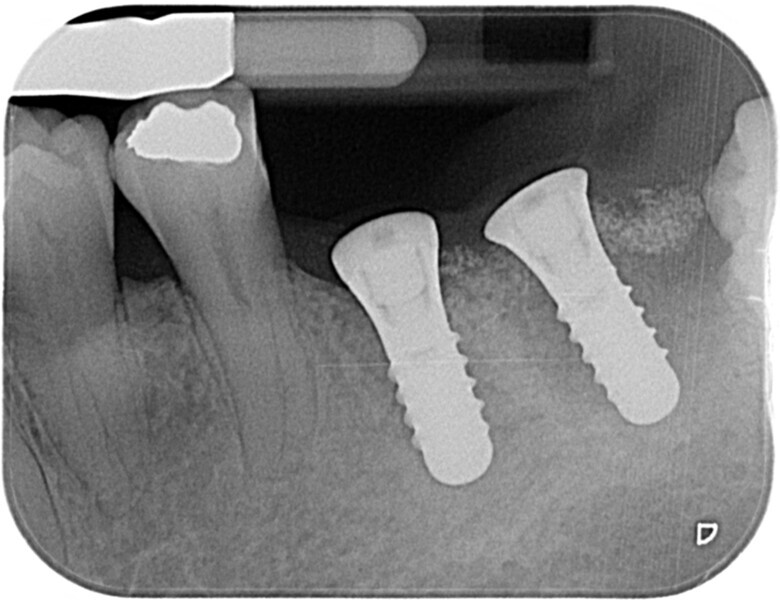

Fig. 8: Postoperative radiograph of implant placement.